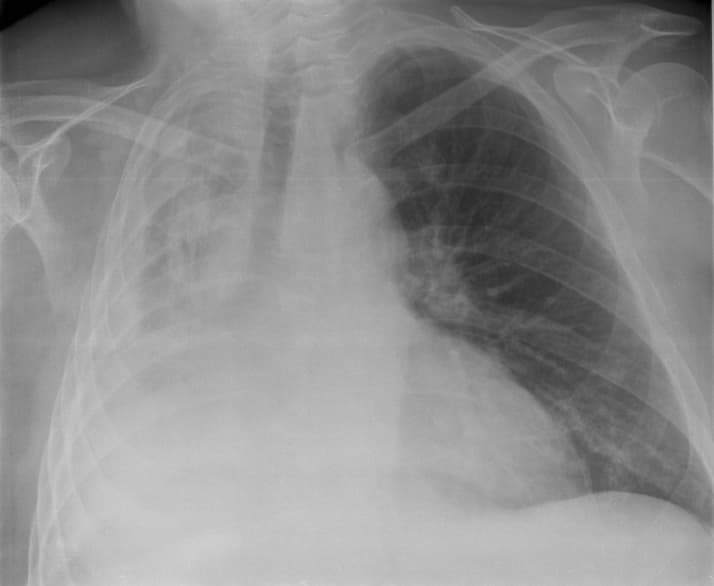

Atelectasis is the collapse or closure of a lung resulting in reduced or absent gas exchange. It is usually unilateral, affecting part or all of one lung. It is a condition where the alveoli are deflated down to little or no volume, as distinct from pulmonary consolidation, in which they are filled with liquid. It is often called a collapsed lung, although that term may also refer to pneumothorax. It is a very common finding in chest X-rays and other radiological studies, and may be caused by normal exhalation or by various medical conditions. Although frequently described as a collapse of lung tissue, atelectasis is not synonymous with a pneumothorax, which is a more specific condition that can cause atelectasis. Acute atelectasis may occur as a post-operative complication or as a result of surfactant deficiency. In premature babies, this leads to infant respiratory distress syndrome. The term uses combining forms of atel- + ectasis, from ἀτελής, "incomplete" + ἔκτασις, "extension". May have no signs and symptoms or they may include: cough, but not prominent; chest pain (not common); breathing difficulty (fast and shallow); low oxygen saturation; pleural effusion (transudate type); cyanosis (late sign); increased heart rate. It is a common misconception and pure speculation that atelectasis causes fever. A study of 100 post-op patients followed with serial chest X-rays and temperature measurements showed that the incidence of fever decreased as the incidence of atelectasis increased. A recent review article summarizing the available published evidence on the association between atelectasis and post-op fever concluded that there is no clinical evidence supporting this speculation. The most common cause is post-surgical atelectasis, characterized by splinting, i.e. restricted breathing after abdominal surgery. Atelectasis develops in 75–90% of people undergoing general anesthesia for a surgical procedure. Another common cause is pulmonary tuberculosis. Smokers and the elderly are also at an increased risk.